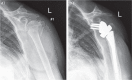

Since the introduction of reverse total shoulder arthroplasty (RTSA) in 1987 (in Europe) and 2004 (in the United States), the number of RTSAs performed annually has increased.Although the main indication for RTSA has been rotator cuff tears, indications have expanded to include several shoulder conditions, many of which involve dysfunction of the rotator cuff.RTSA complications have been reported to affect 19% to 68% of patients and include acromial fracture, haematoma, infection, instability, mechanical baseplate failure, neurological injury, periprosthetic fracture and scapular notching.Current controversies in RTSA include optimal baseplate positioning, humeral neck-shaft angle (135° versus 155°), glenosphere placement (medial, lateral or bony increased offset RTSA) and subscapularis repair.Improvements in prosthesis design, surgeon experience and clinical results will need to occur to optimize this treatment for many shoulder conditions. Cite this article: EFORT Open Rev 2018;3:58-69 DOI: 10.1302/2058-5241.3.170044.